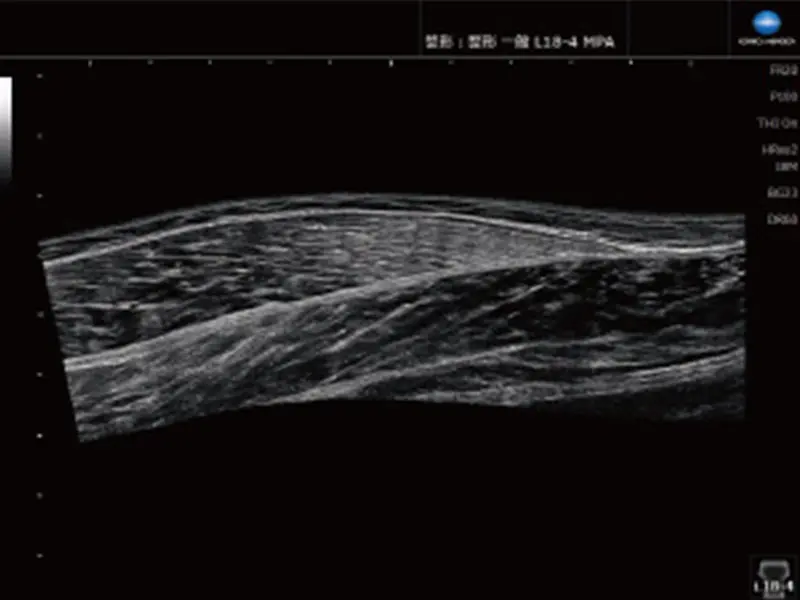

より広い領域を一画面に

パノラミックビュー

プローブをスライドさせるだけの簡単操作により広範囲な画像を取得できます。解剖学的な位置関係の把握に役立ちます。

対応プローブ:L18-4、L11-3、L14-4